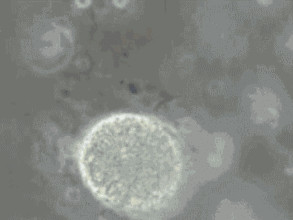

精子DNA的完整性,與精子功能有顯著相關性,并且可以影響受精卵的分裂以及胚胎的發育。DNA位于精子的細胞核內,是遺傳信息的載體,位置類似雞蛋的蛋黃。精子DNA 損傷后,雖然看上去是“好”的,但其功能變差了,盡管不影響卵子受精,但容易導致胚胎發育不良和流產。精子DNA損傷嚴重的患者,即使可使卵子正常受精、分裂,但最后仍然可以導致流產。